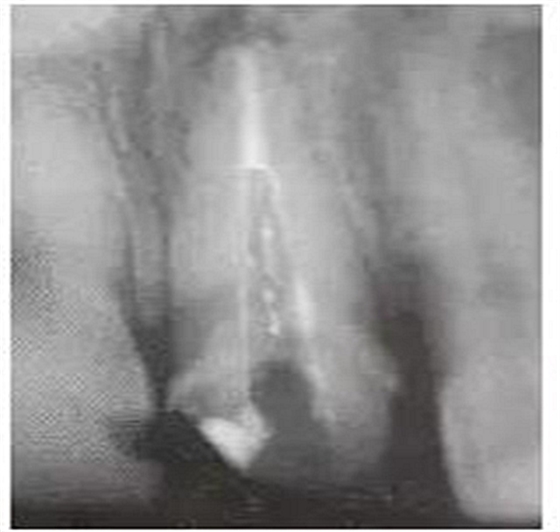

預(yù)備后根管壁上會(huì)不同程度的牙膠和封閉劑等殘留物,所以樁道預(yù)備前后建議X線片輔助檢查預(yù)備深度等情況,而殘留物也會(huì)很清晰地顯現(xiàn)。

根管銼去除殘留物,很難去除干凈,而備取樁道時(shí),禁止使用牙膠溶解劑(如:丁克除、氯仿)等有機(jī)溶劑去除殘留物,以防破壞根尖區(qū)牙膠的封閉和防止附著根管壁影響粘接。(超聲去除根管殘留物)

通常此時(shí)以超聲潔牙機(jī)更換較細(xì)工作尖進(jìn)入根管(根管消毒沖洗液配合清潔工作后面會(huì)提到),徹底去除樁道根管壁上的附著殘留物,效果明顯。再配合X線片、根管顯微鏡輔助檢查清理的情況下更佳。